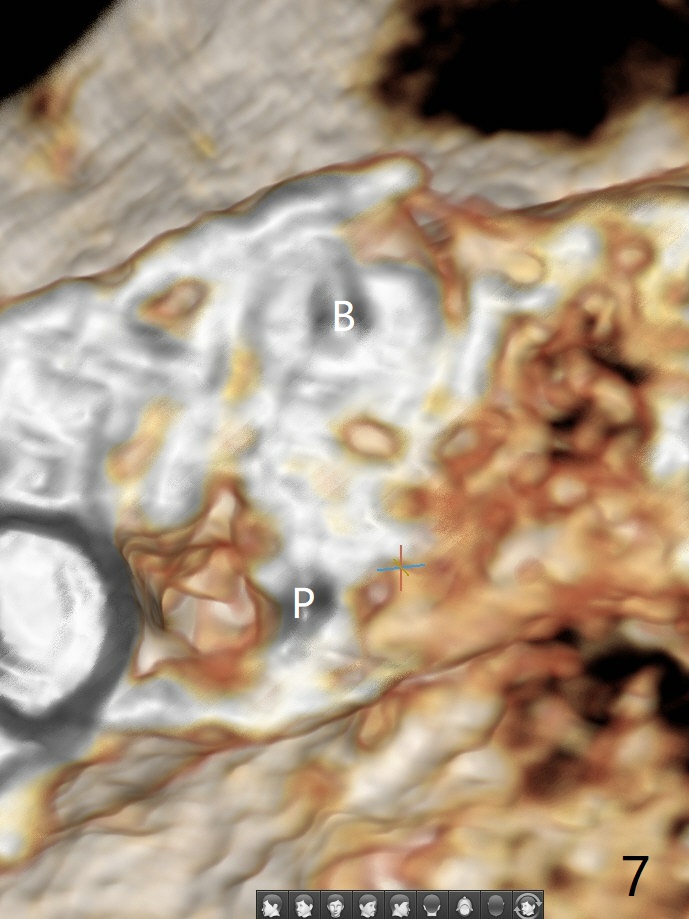

52岁女左上4颊侧牙龈显著肿胀(图一:*(颊侧骨板缺失))伴有瘘道(<),拔除前,在3植牙牙冠切缘舌侧形成开口(图二:*,准备纠正基台不全就位(<);4初步钻洞不正。改变钻头方向后(图三),完成植体放置(图四),并且安置修复基台(4.5x4(2))。磨去3牙冠近中面(图六:*),牙冠和基台反时针旋转(图六:弯箭头),基台完全就位(图四:箭头),调𬌗后,制作4临时牙冠(图六),放置后者前,覆盖半张PRF膜(促进下面粘性骨粉愈合)。图五,六颊侧隆起是因为下面放置许多粘性骨粉。图七是术前CT3D图像(冠状切面),显示颊侧(B),腭侧(P)牙根。拔牙后显示中隔(图八:S),植体植入腭侧窝(图九:绿色),四面骨质包绕,包括中隔;为了修复颊侧骨板,首先放置半张PRF膜(红色)紧贴颊侧骨板腭侧/牙龈,防止骨粉从瘘道流失,然后放置粘性骨粉(图十:粉红色)。术后2.5月3颊侧牙龈仍然红肿(图十一,十二:*),可能与基台袖太短有关(2毫米,图二至四),所以更换袖3毫米的基台(图十三)。术后四个月(牙冠粘固)3颊侧牙龈炎症明显减退(资料没有显示)。术后2.5月4颊侧骨板没有塌陷(图十二,与术后即刻对比(图六))。3基台放置太颊侧,所以在牙冠腭侧制作小的开口(图十四:>),让多余粘固剂流出。取模前3螺丝就拧紧(35Ncm),而4由于有大的开口,粘固后才拧紧(30Ncm)。两个邻牙其中一个可以取出,容易去除另外一个牙冠残余粘固剂。